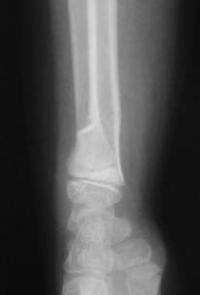

Fracture métaphysaire distale du radius  : radio de Face à J15

Contrôle radio de Face à J15 de la fracture traitée par plâtre brachio-palmaire